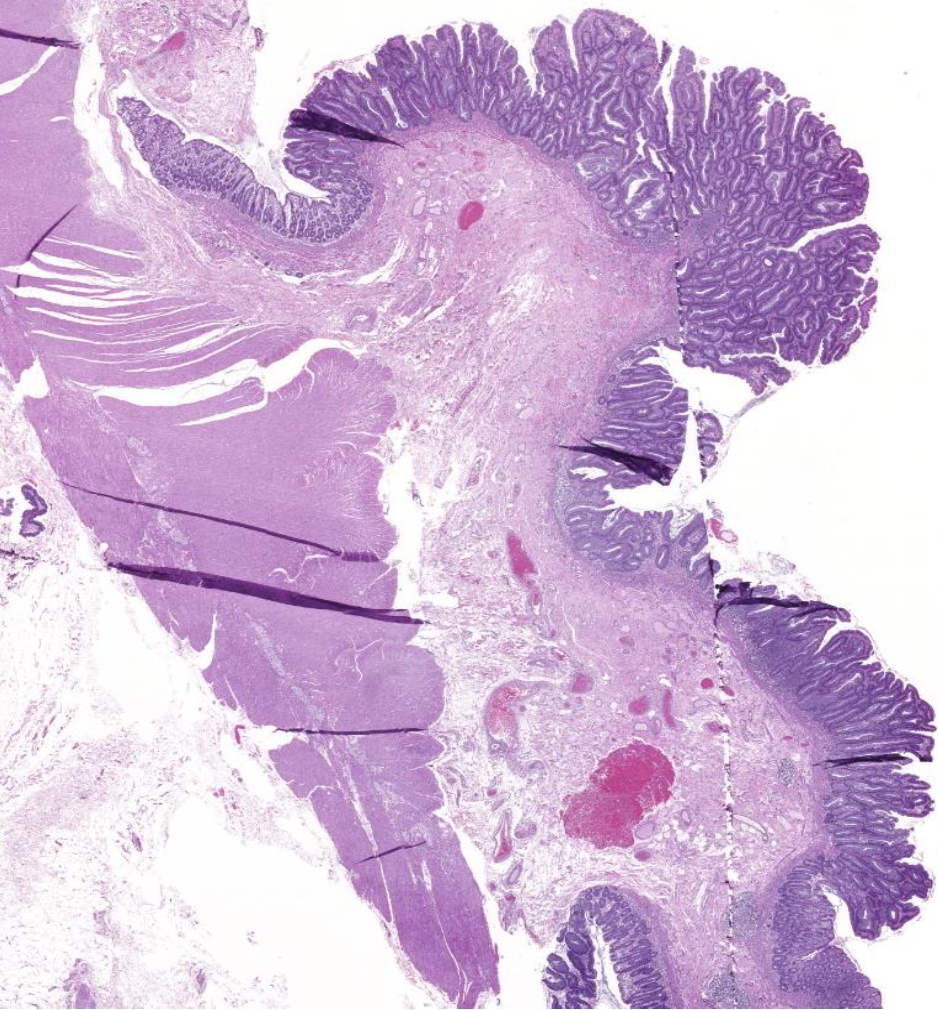

Diagnose?

Barettmetaplasie mit Dysplasie

-> Erkennt man an Becherzellen